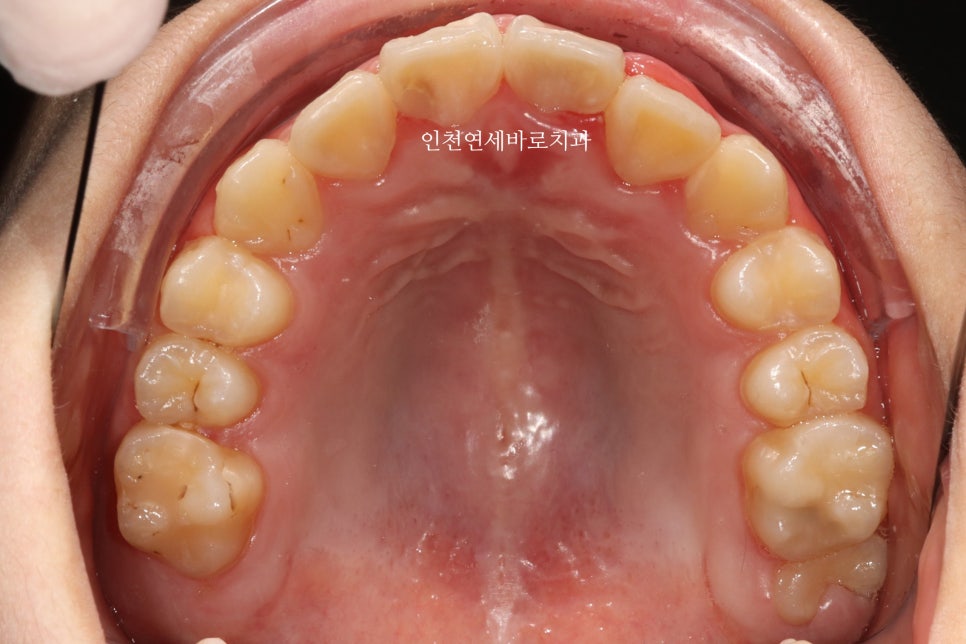

그리고 올해 12월 초에 병원에 왔을 때의 모습입니다.

100점은 아니지만, 이제는 거의 모든 치아가 배열된 것 처럼 보입니다.